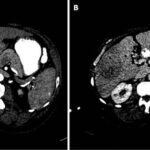

El Liver Cancer Study Group of Japan, en 2009, propuso una clasificación basada en el patrón de crecimiento tumoral, que es muy útil para el diagnóstico por imagen, ya que describe la apariencia macroscópica de la infiltración y de esta manera se complementa con los hallazgos encontrados en las pruebas de imágenes permitiendo realizar un diagnóstico diferencial. Clasifica los tumores en tres grupos: los formadores de masa, los de infiltración predominantemente periductal (Anexo 16) y los de crecimiento intraductal. Existe predominio de un patrón de crecimiento u otro en función de la localización topográfica: el colangiocarcinoma intrahepático suele debutar como una masa, mientras que en los colangiocarcinomas hiliar y extrahepático predomina la infiltración periductal.

El reforzamiento en anillo (hipercaptación periférica) o incluso menos de 25% de la lesión, y es más frecuente en nódulos mayores a 3 cm. En la fase venosa portal puede permanecer invariable cuando los nódulos son pequeños. Puede presentar un reforzamiento progresivo: existiendo el máximo realce en fases tardías (más frecuentes en nódulos de mayor tamaño). También puede demostrar un reforzamiento continuo con área central que no capta el medio de contraste. En la fase tardía la región central puede mostrar un reforzamiento variable en función de la existencia de fibrosis (aumento de la captación) o necrosis coagulativa (sin captación del contraste).(18-22)